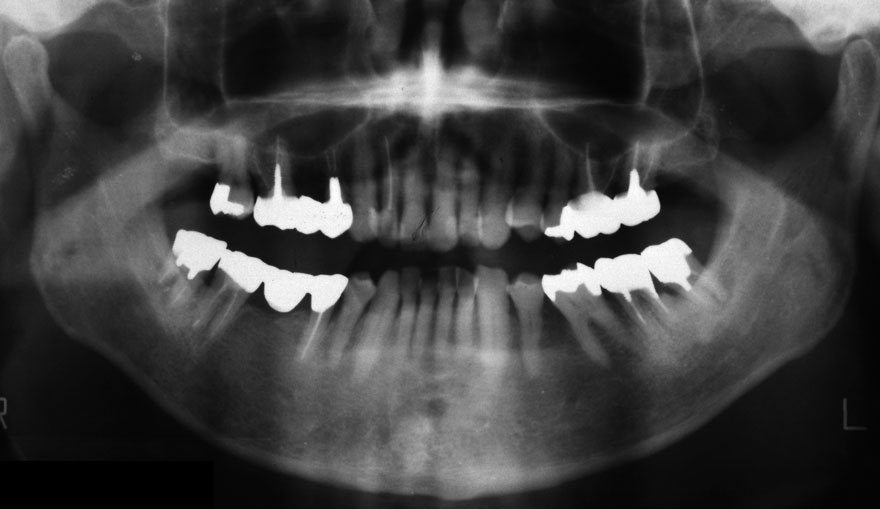

開始年齢 30代

初診時 30歳 女性 平均歯槽骨喪失量:1.46mm

22年後 52歳

平均歯槽骨喪失量:1.55mm

22年間喪失量:-0.09mm

年間喪失速度:-0.004mm

(ケア頻度:1.76ヵ月ごと)